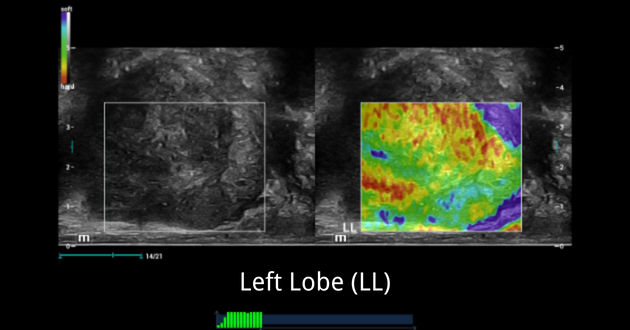

Ultrasound Findings of left lobe of the prostate:

NTE ŌĆō Strain Elastography:

SWE ŌĆō Shear Wave Elastography:

- NTE showed a very stiff area which was linked with hypoechoic area in 2D of RL. LL showed typically normal findings with a soft elastogram map and a well-defined border between TZ and PZ.

- While SWE showed normal stiffness measurements of LL, which mean stiffness value was 19kPa and max stiffness value was 36kPa.

Combined NTE and SWE results, we had more clinical evidence to confidently confirm that this patient had local PCa on RL, and LL of prostate seems to be normal.